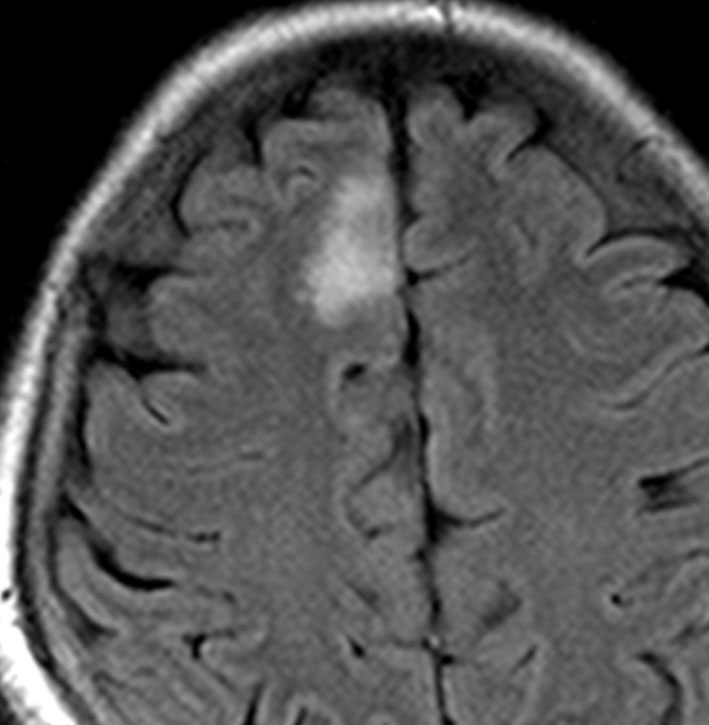

• MRI-T1強調画像では低信号となり,T2強調画像とフレア画像では高信号域となります

• グリオーマの中では,T2強調画像での腫瘍内部のコントラストが強く,石灰化の部分は強い低信号域として,のう胞は均一な強い高信号域となります

• 周囲脳組織浮腫あるいは腫瘍浸潤部は淡い高信号域として描出されます

• 脳浮腫を伴うものはグレード3の可能性が高いです

• ガドリニウムによる造影では,悪性度が高くなるにつれて部分的な増強像が増えます

平均的な増大速度を示した乏突起膠腫グレード2です。左が無症状で発見された時,右が3年後で,ごくわずかに増大しています。開頭手術で摘出しました。